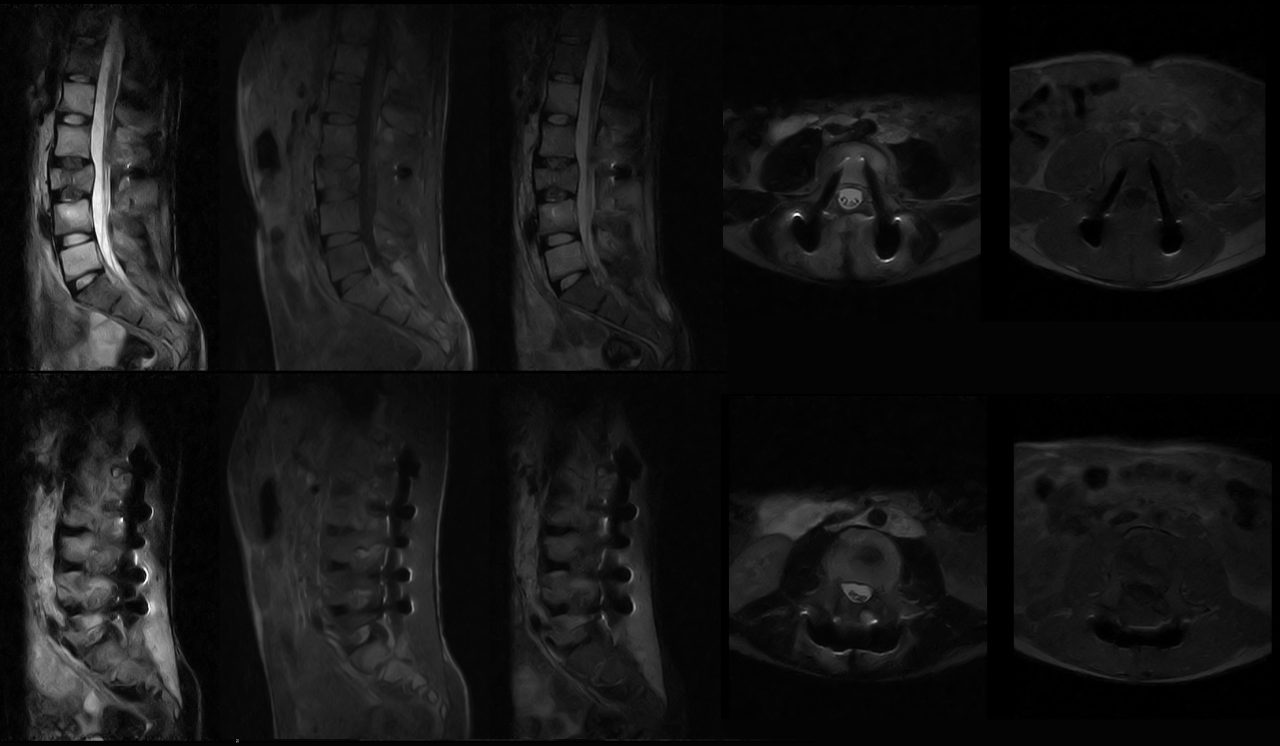

Os implantes metálicos podem criar artefatos nas imagens de ressonância magnética, como áreas escuras ou claras que não correspondem à realidade anatômica do paciente. Além disso, a presença de metais pode causar aquecimento localizado nos tecidos, representando um risco para a segurança do paciente. Esses desafios têm limitado o uso efetivo da ressonância magnética em pacientes com implantes metálicos, resultando em alternativas menos precisas ou invasivas para o diagnóstico médico.

- Imagens de alta qualidade: A ressonância magnética de campo aberto e baixo campo permite a obtenção de imagens de alta qualidade. Isso é possível graças aos avanços na tecnologia de processamento de sinal, que compensa as distorções causadas pelos implantes metálicos.

- Menos distorções nas imagens: A interferência causada pelos implantes metálicos é minimizada na ressonância magnética de campo aberto e baixo campo, resultando em menos distorções nas imagens. Isso permite que os médicos obtenham uma visão mais precisa e detalhada das estruturas internas do corpo humano, facilitando o diagnóstico e o planeamento do tratamento.